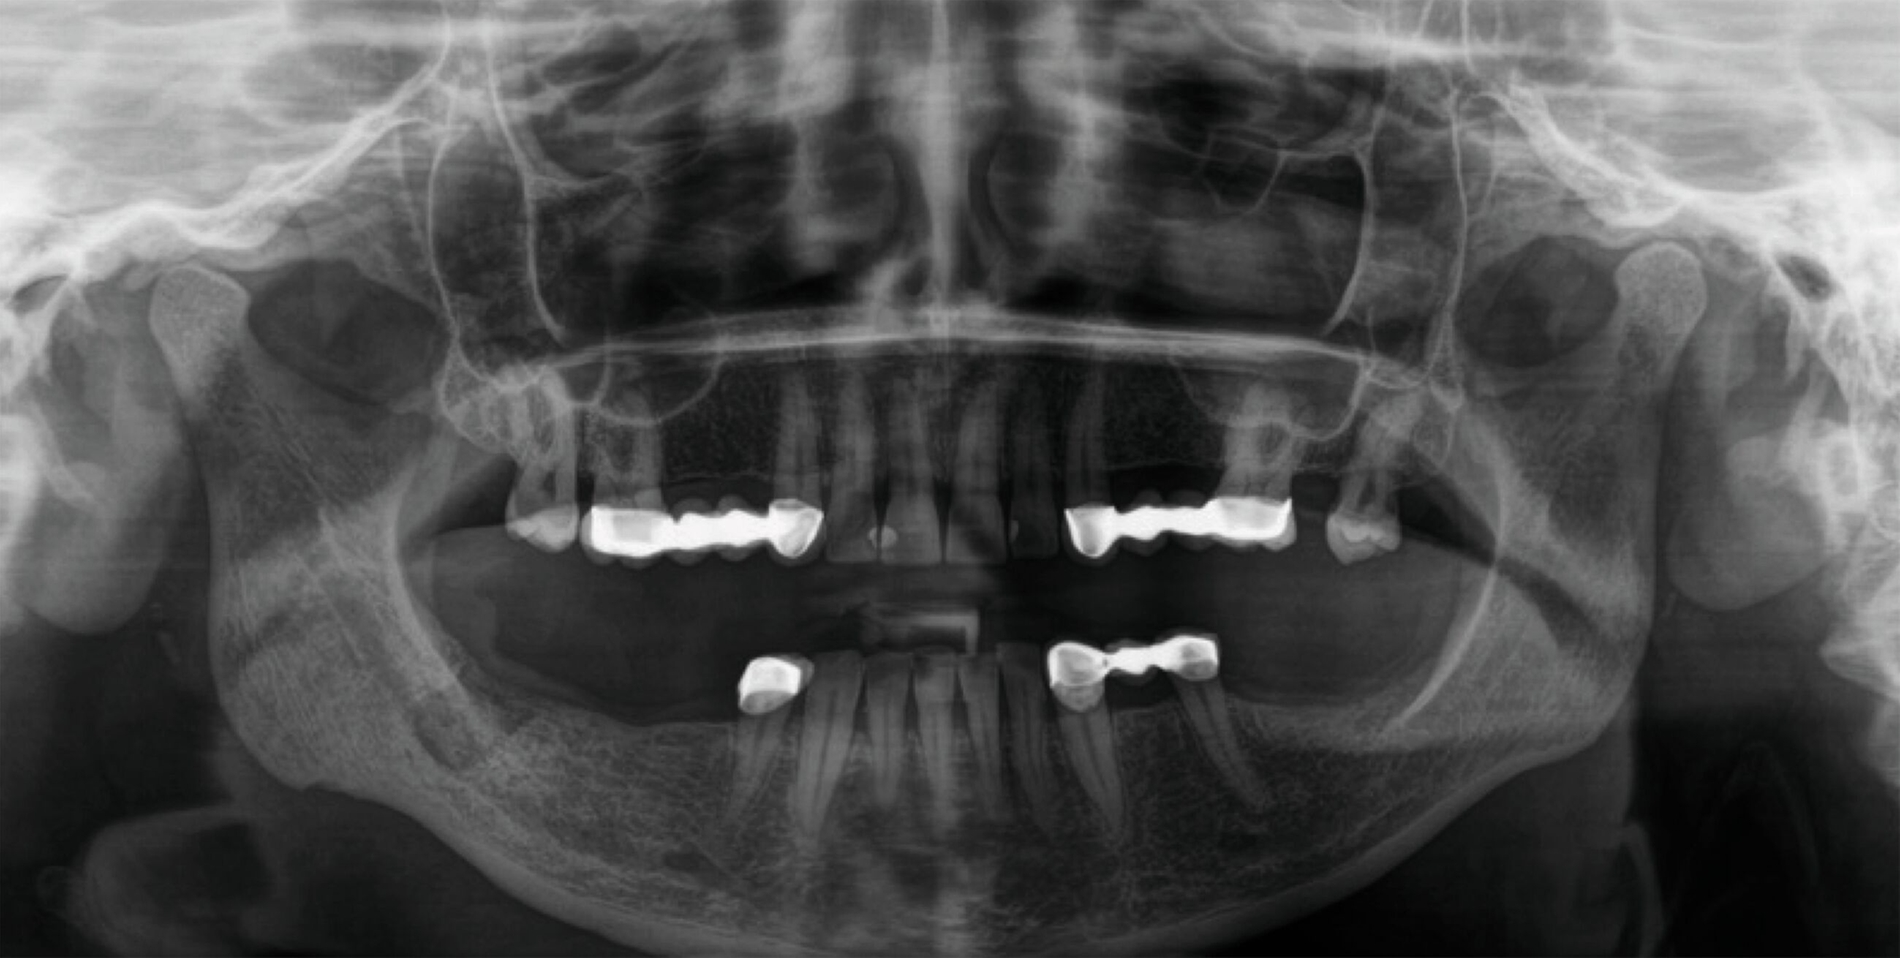

In der klinischen Untersuchung zeigte sich der submandibuläre Volumendefekt rechts im Bereich der alten Narbe der Submandibulektomie. Zusätzlich zeigte sich zum Untersuchungszeitpunkt submandibulär rechts ein Fistelmaul. Die Haut im Bereich des alten OP-Gebietes war narbig und derb strukturiert und teilweise mit dem subkutanen Gewebe verbacken. Die Sensibilität zeigte mit Ausnahme des Bereiches der alten Operationsnarbe eine Normästhesie, die lokale Gewebeperfusion erschien soweit klinisch beurteilbar unauffällig. Die Funktion des N. facialis war bis auf eine leichte iatrogene Schädigung des N. marginalis und damit eines gering hängenden rechten Mundwinkels regelgerecht. Die Patientin hatte keine Schmerzen im Bereich des Volumendefekts, die Beweglichkeit des Halses war uneingeschränkt. Im Zuge der intraoralen Untersuchung und der begleitenden zahnärztlichen Bildgebung zeigte sich ein nicht erhaltungswürdiger Zahn 48 mit einer apikalen Entzündung, der gemeinsam mit der nach extraoral reichenden Fistel und dem extraoral gelegenen Fistelmaul entfernt wurde (Abbildung 2).